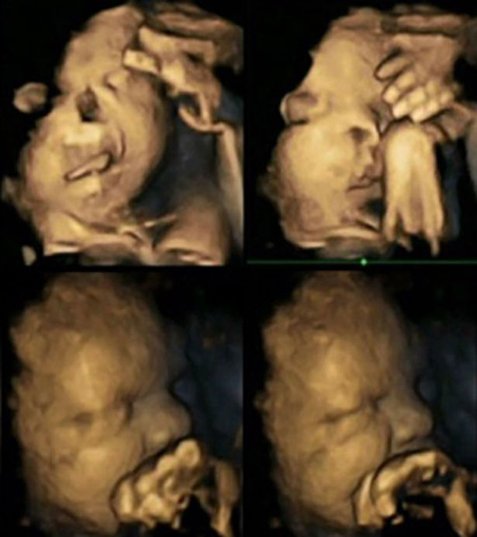

Επιστήμονες στη Βρετανία είναι σε θέση να πιστεύουν ότι θα μπορούν πια όχι μόνο με τα λόγια, αλλά με αδιάψευστες εικόνες να δείξουν στις γυναίκες που καπνίζουν συστηματικά κατά τη διάρκεια της κύησης πώς αντιδρά το έμβρυο στις ουσίες του τσιγάρου μέσα από τη μήτρα. Επικεφαλής της έρευνας είναι η δρ. Νάγια Ρέισλαντ από το Πανεπιστήμιο του Ντάραμ, η οποία με υπερηχογράφους 4-D κατάφερε να απεικονίσει τις αντιδράσεις των εμβρύων στις ουσίες του τσιγάρου. Η δρ. Νάγια Ρέισλαντ διαπίστωσε ότι τα έμβρυα των γυναικών που κάπνιζαν περίπου 14 τσιγάρα την ημέρα, παρουσίαζαν έντονη κινητικότητα στο στόμα, ενώ άγγιζαν συνεχώς την περιοχή του στόματος και της μύτης με τα χέρια τους. Αντιθέτως, όσα δεν εκτίθονταν στις ουσίες του τσιγάρου, παρουσίασαν φυσιολογική συμπεριφορά, χωρίς αυξημένη κινητικότητα στις προαναφερθείσες περιοχές. Η γιατρός παρακολούθησε 20 μητέρες εκ των οποίων οι τέσσερις κάπνιζαν κατά μέσο όρο 14 τσιγάρα την ημέρα.

Η πιλοτική μελέτη ελπίζει να διευρύνει το δείγμα της έρευνας σε περισσότερες γυναίκες ώστε να διαπιστώσει αν πράγματι το κάπνισμα κατά τη διάρκεια της εγκυμοσύνης επηρεάζει σημαντικά την ανάπτυξη του νευρικού συστήματος των εμβρύων. Η δρ. Νάγια Ρέισλαντ ευχαρίστησε όλες τις γυναίκες που συμμετείχαν εθελοντικά στην έρευνα και κυρίως τις καπνίστριες. Διαβεβαίωσε, επίσης, ότι τα μωρά όλων αυτών των γυναικών γεννήθηκαν χωρίς κανένα πρόβλημα υγείας.